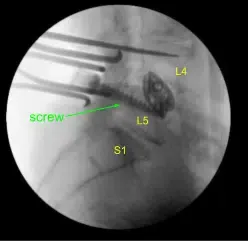

Given the concern for the implant in the prone position and our feeling that the endplates may have fractured more, we exposed the transverse processes for L4 and L5 and used the drill to create pilot holes in the pedicle on the left side at L4 and L5. Under fluoroscopy, we guided probes through the pedicles and tapped each pedicle, then placed pedicle screws into L4 and L5.